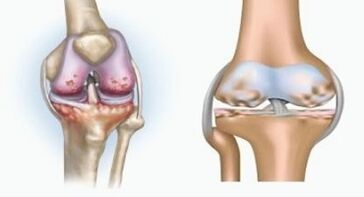

Beide Pathologien beeinflussen die Gelenke, unterscheiden sich jedoch in der Art der Veränderungen.

Mit Arthritis

Arthritis ist eine Entzündung des Bindegewebes - eine Synovialmembran, die viele Gefäße enthält und Lymphstrom liefert. Der Entzündungsprozess führt zu einer Verletzung der Ernährung von Gelenkgeweben, wobei die Produktion von Gelenkschmierung - Synovialflüssigkeit begrenzt ist.

Mit Arthrose

Arthrose ist ein degenerativ-dystrophischer Prozess, der mit der Zerstörung des Knorpelgewebes des Gelenks verbunden ist. Der Knorpel wird allmählich zerstört, trocken, der Abstand zwischen den Gelenkknochen nimmt ab, was die Ursache für Schmerzen ist. In schweren Formen beeinflusst die Zerstörung Knochen. Sie werden poröser, verlieren ihre Dichte, werden zerbrechlich.

Was ist zum Beispiel der Unterschied zwischen Arthritis und Arthrose des Kniegelenks? Bei Arthritis tritt die synoviale Hülle von Gelenkgeweben auf. Dies führt zu einer Erhöhung der Temperatur im Gelenk.

Das Gelenk schwillt, ein anhaltendes Schmerzsyndrom entwickelt sich und verstärkt sich während der Bewegung. Bei Arthrose treten der Schmerz erst nach körperlicher Aktivität auf, Sie können einen charakteristischen Crunch oder Klicks im Gelenk hören, allmählich ist das Gelenk deformiert und verliert Mobilität.